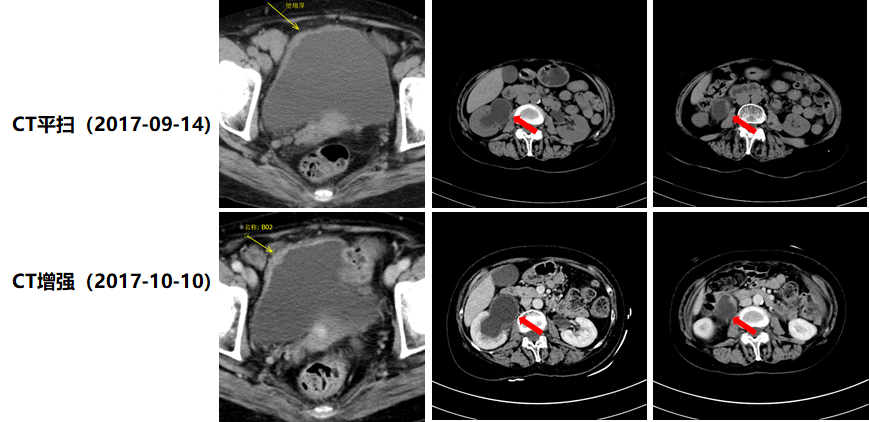

2019年6月4日,患者开始接受一线信迪利单抗(200mg,ivgtt,Q3W)单药治疗,4周期治疗后,于2019年9月2日复查CT示:前“2019年4月23日”术区右侧腰大肌旁软组织密度影,本次未显示。前肝右下叶片状稍低密度影,本次未显示(图3)。疗效评价为CR。截至2019年12月28日,患者一线治疗无进展生存期(PFS1)已达6个月。

image003.png

图3.患者接受信迪利单抗一线治疗4周期后疗效评价为CR